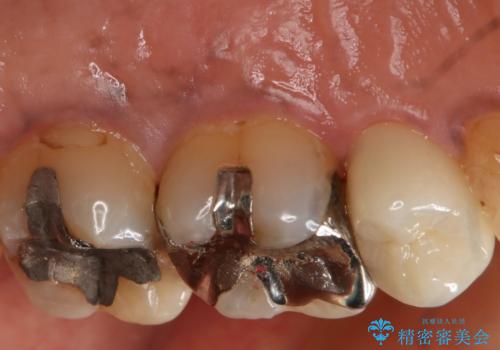

- 左上5番根尖部歯肉に膿ができ、治療を希望された患者様です。

神経が失活し根尖病変も見られるので、精密根管治療とクラウンでの治療を計画しました。

セラミックでの治療を希望されたので、フルジルコニアクラウンでの治療を選択しました。